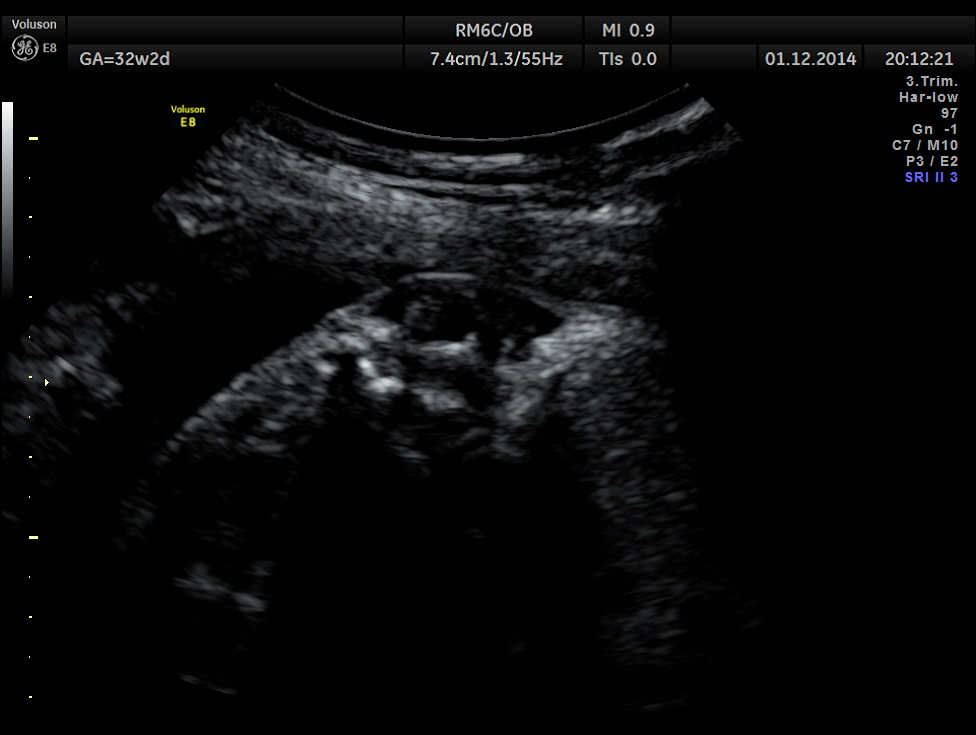

This was a 30 year old lady , with history of consanguinity ; 2nd gravida , 1st child normal ; she has never gone for an ultrasound examination in this pregnancy and was sent by her consultant to a different centre for evaluation . She was found to have hydrocephalus and was referred to our clinic for 2nd opinion.

The following images were obtained.

Hydrocephalus is seen ; Cisterna magna appeared somewhat compressed.